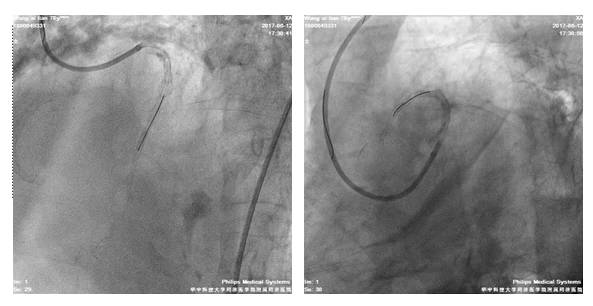

我院冠脉造影

LM严重钙化,体部散在斑块;LAD近段-中段弥漫性钙化伴狭窄,最重处约70%

LCX弥漫性钙化伴狭窄,最重处狭窄约90%

RCA开口处严重钙化,近中段弥漫性狭窄,中段最重狭窄达90%,狭窄最重处达90%,伴溃疡

6F JR4.0/GC

BMW/GW

2.5*20mmTazuna扩RCA中段8-16atm

3.0*33mm DES置入RCA中段

3.5*36mmDES置入RCA近段10-14atm,与前支架串联

3.5*15mm Hiryu 扩RCA8-20atm

术后造影

四日后,尝试左冠PCI术

股动脉路径

7F EBU3.5/GC

Runthrough NS,ASAHI SION,BMW导丝

2.5*20mm球囊扩张LAD10*12atm

先后与LAD远段-近段置入2.5*33mm、2.75*33mm、3.0*29mm DES支架,三支架串联